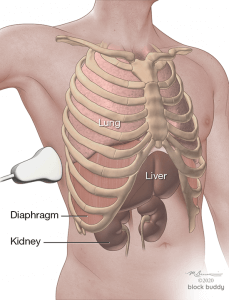

Anatomy

- The ribs will appear as convex hyperechoic lines with acoustic shadows.

- Located between the ribs are the hypoechoic intercostal muscles and the smooth, thin hyperechoic pleural line.

- These structures form the “bat sign”: the shadow of the ribs form the wings, while the area between the ribs represents the body.

- The transducer is placed in the long axis of zone 4, at the level of the diaphragm, near the mid or posterior axillary line.

- A normal exam will reveal the liver/spleen, diaphragm, mirror image of the liver/spleen superior to the diaphragm, and the vertebral column lying posterior to the liver/spine (“spine sign”).